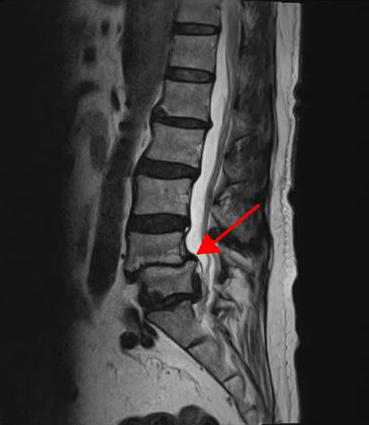

<4-5번 척추전방전위증>

이 환자분의 허리 MRI를 보면 4번, 5번 오른쪽에 심한 추간공협착증과 2단계의 척추전방전위증이 있는데, 특히 척추전방전위증 때문에 추간공이 많이 좁아져 있는 상태입니다. 또 왼쪽의 다른 마디에 디스크 파열이 있으나 환자분이 왼쪽으로는 증상이 전혀 없는 것으로 보아 이 디스크 파열은 통증을 일으키지 않는 무증상의 디스크 파열입니다.

이렇듯 4번, 5번 마디의 심한 추간공협착증과 척추전방전위증으로 인해 이 환자분은 다리에 마비가 왔고, 발목에 힘이 빠져 거의 걷지 못하는 상태였습니다. 새벽에 잠에서 깨 화장실을 갈 때는 네 발로 기어갈 정도로 증상이 심했습니다. 신경주사도 많이 맞아봤지만 통증이 전혀 줄지 않아서 결국 수술을 결심하셨는데요. 대학병원을 비롯해 정형외과 및 신경외과 등 아홉 군데 병원에서 진료를 받았지만, 어려운 수술이라고 말하면서 척추유합술, 감압술 등 병원마다 제시하는 수술방법이 다 달라 큰 혼란을 겪으셨습니다. 게다가 수술 후 후유증이나 잔존 증상에 대한 물음에 ‘있을 수도 있고 없을 수도 있다’라는 의사의 말에 수술을 고민하던 중 마지막이라는 생각으로 저희 모커리에 내원하셨습니다.

이 환자분처럼 상태가 매우 심각한 중증 협착증, 2단계 이상의 척추전방전위증도 허리 주변 근육의 기능을 회복하고, 문제를 해결해주는 근육재활치료를 통해 수술 없이 충분히 치료가 가능합니다.

그 이유는 척추관이 매우 심하게 좁아졌거나, 또는 척추 뼈가 많이 밀려나갔어도 허리 주변 근육의 상태가 좋고, 근육이 제 기능을 잘하고 있으면 통증이 없거나 통증이 훨씬 덜합니다. 그래서 허리 주변 근육의 기능을 회복시키는 근육재활치료를 잘해주면 척추전방전위증, 협착증 증상이 많이 좋아질 수 있는 것입니다.